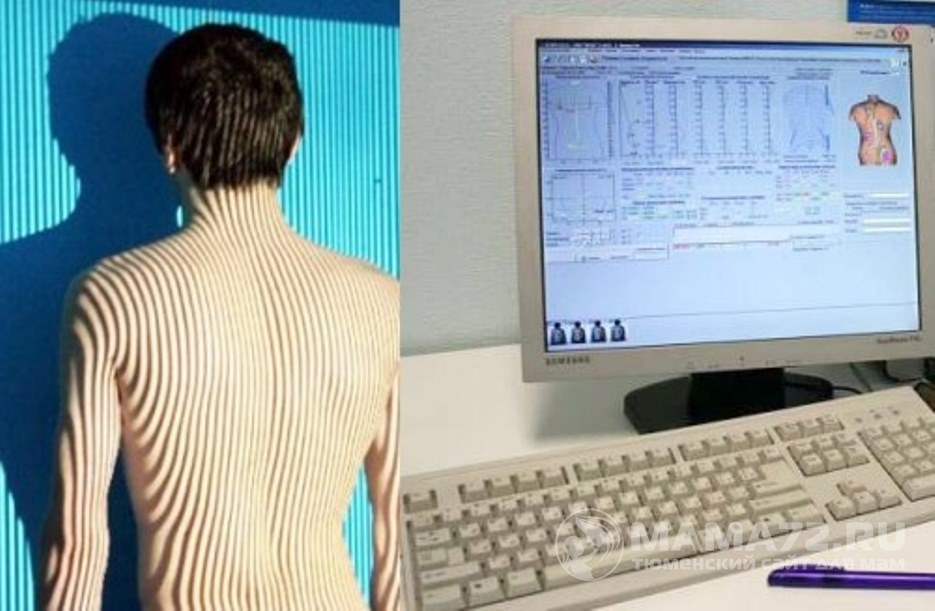

Оптическая диагностика позвоночника Diers: изображения и технологии

Раздел: Мир в картинках